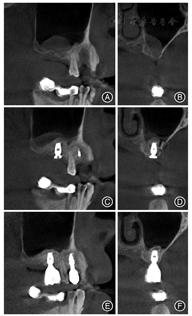

囊肿组典型病例 患者,男,56岁,2017年4月就诊,主诉:右上牙齿缺失。现病史,右上牙齿因松动拔除数年,要求种植修复。检查:14、16、17缺失,缺牙区宽度可,龈无明显红肿,CBCT示16的RBH约3 mm,16牙位区远中上颌窦底约11 mm × 5 mm穹窿型低密度影,无明显包膜影像。诊断:右上颌牙列缺损。治疗:14行种植修复、16行上颌窦底外提升术同期种植术,种植一期手术6个月后行种植修复。于2017年4月行14种植体植入,16行经外侧壁开窗的上颌窦底提升术同期植入种植体,术中将上颌窦底黏膜剥离,完整将窦底黏膜及囊肿提升,术后CBCT示提升效果可,囊肿未破溃。术后6个月行二期修复。修复后12个月随访,CBCT示种植体无明显骨吸收,上颌窦提升成骨效果可,16远中上颌窦底囊肿已消退。该患者手术前后及随访CBCT影像见图1。